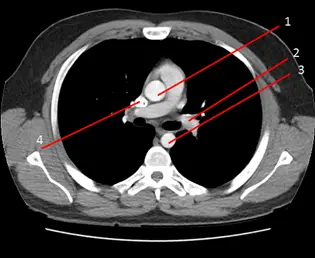

下圖為 chest CT影像,升主動脈( ascending aorta )位於下列那一個編號?

提供的圖片為一張施打靜脈對比劑的胸部電腦斷層軸狀面影像(Axial contrast-enhanced chest CT),使用縱膈腔窗(Mediastinal window)顯示。 在肺動脈幹分叉的層次,我們可以依序辨識出以下重要標號的解剖構造:

- 編號 1:位於縱膈腔前中半部,呈現巨大、圓形且內部充滿對比劑高訊號的血管結構。此為升主動脈(Ascending aorta)。

- 編號 2:位於升主動脈的後方及左側(影像的右方),正在向左後方延伸的血管,此為**主肺動脈(Main pulmonary artery)延伸至左肺動脈(Left pulmonary artery)**的位置。

- 編號 3:位於縱膈腔後方,緊貼著胸椎椎體左